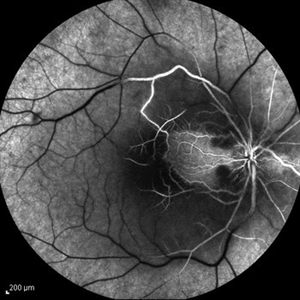

Behcet's Disease Behcet's DiseaseMar 13 2013 by Hamid Ahmadieh, MD Late phase FA of the right eye of a 23-year-old man with retinal vasculitis and branch retinal vein occlusion (BRVO) due to Behcet's disease . Photographer: Solmaz Shahmohammad, Negah Eye Center, Tehran Imaging device: Heidelberg Spectralis Condition/keywords: branch retinal vein occlusion (BRVO), retinal vasculitis